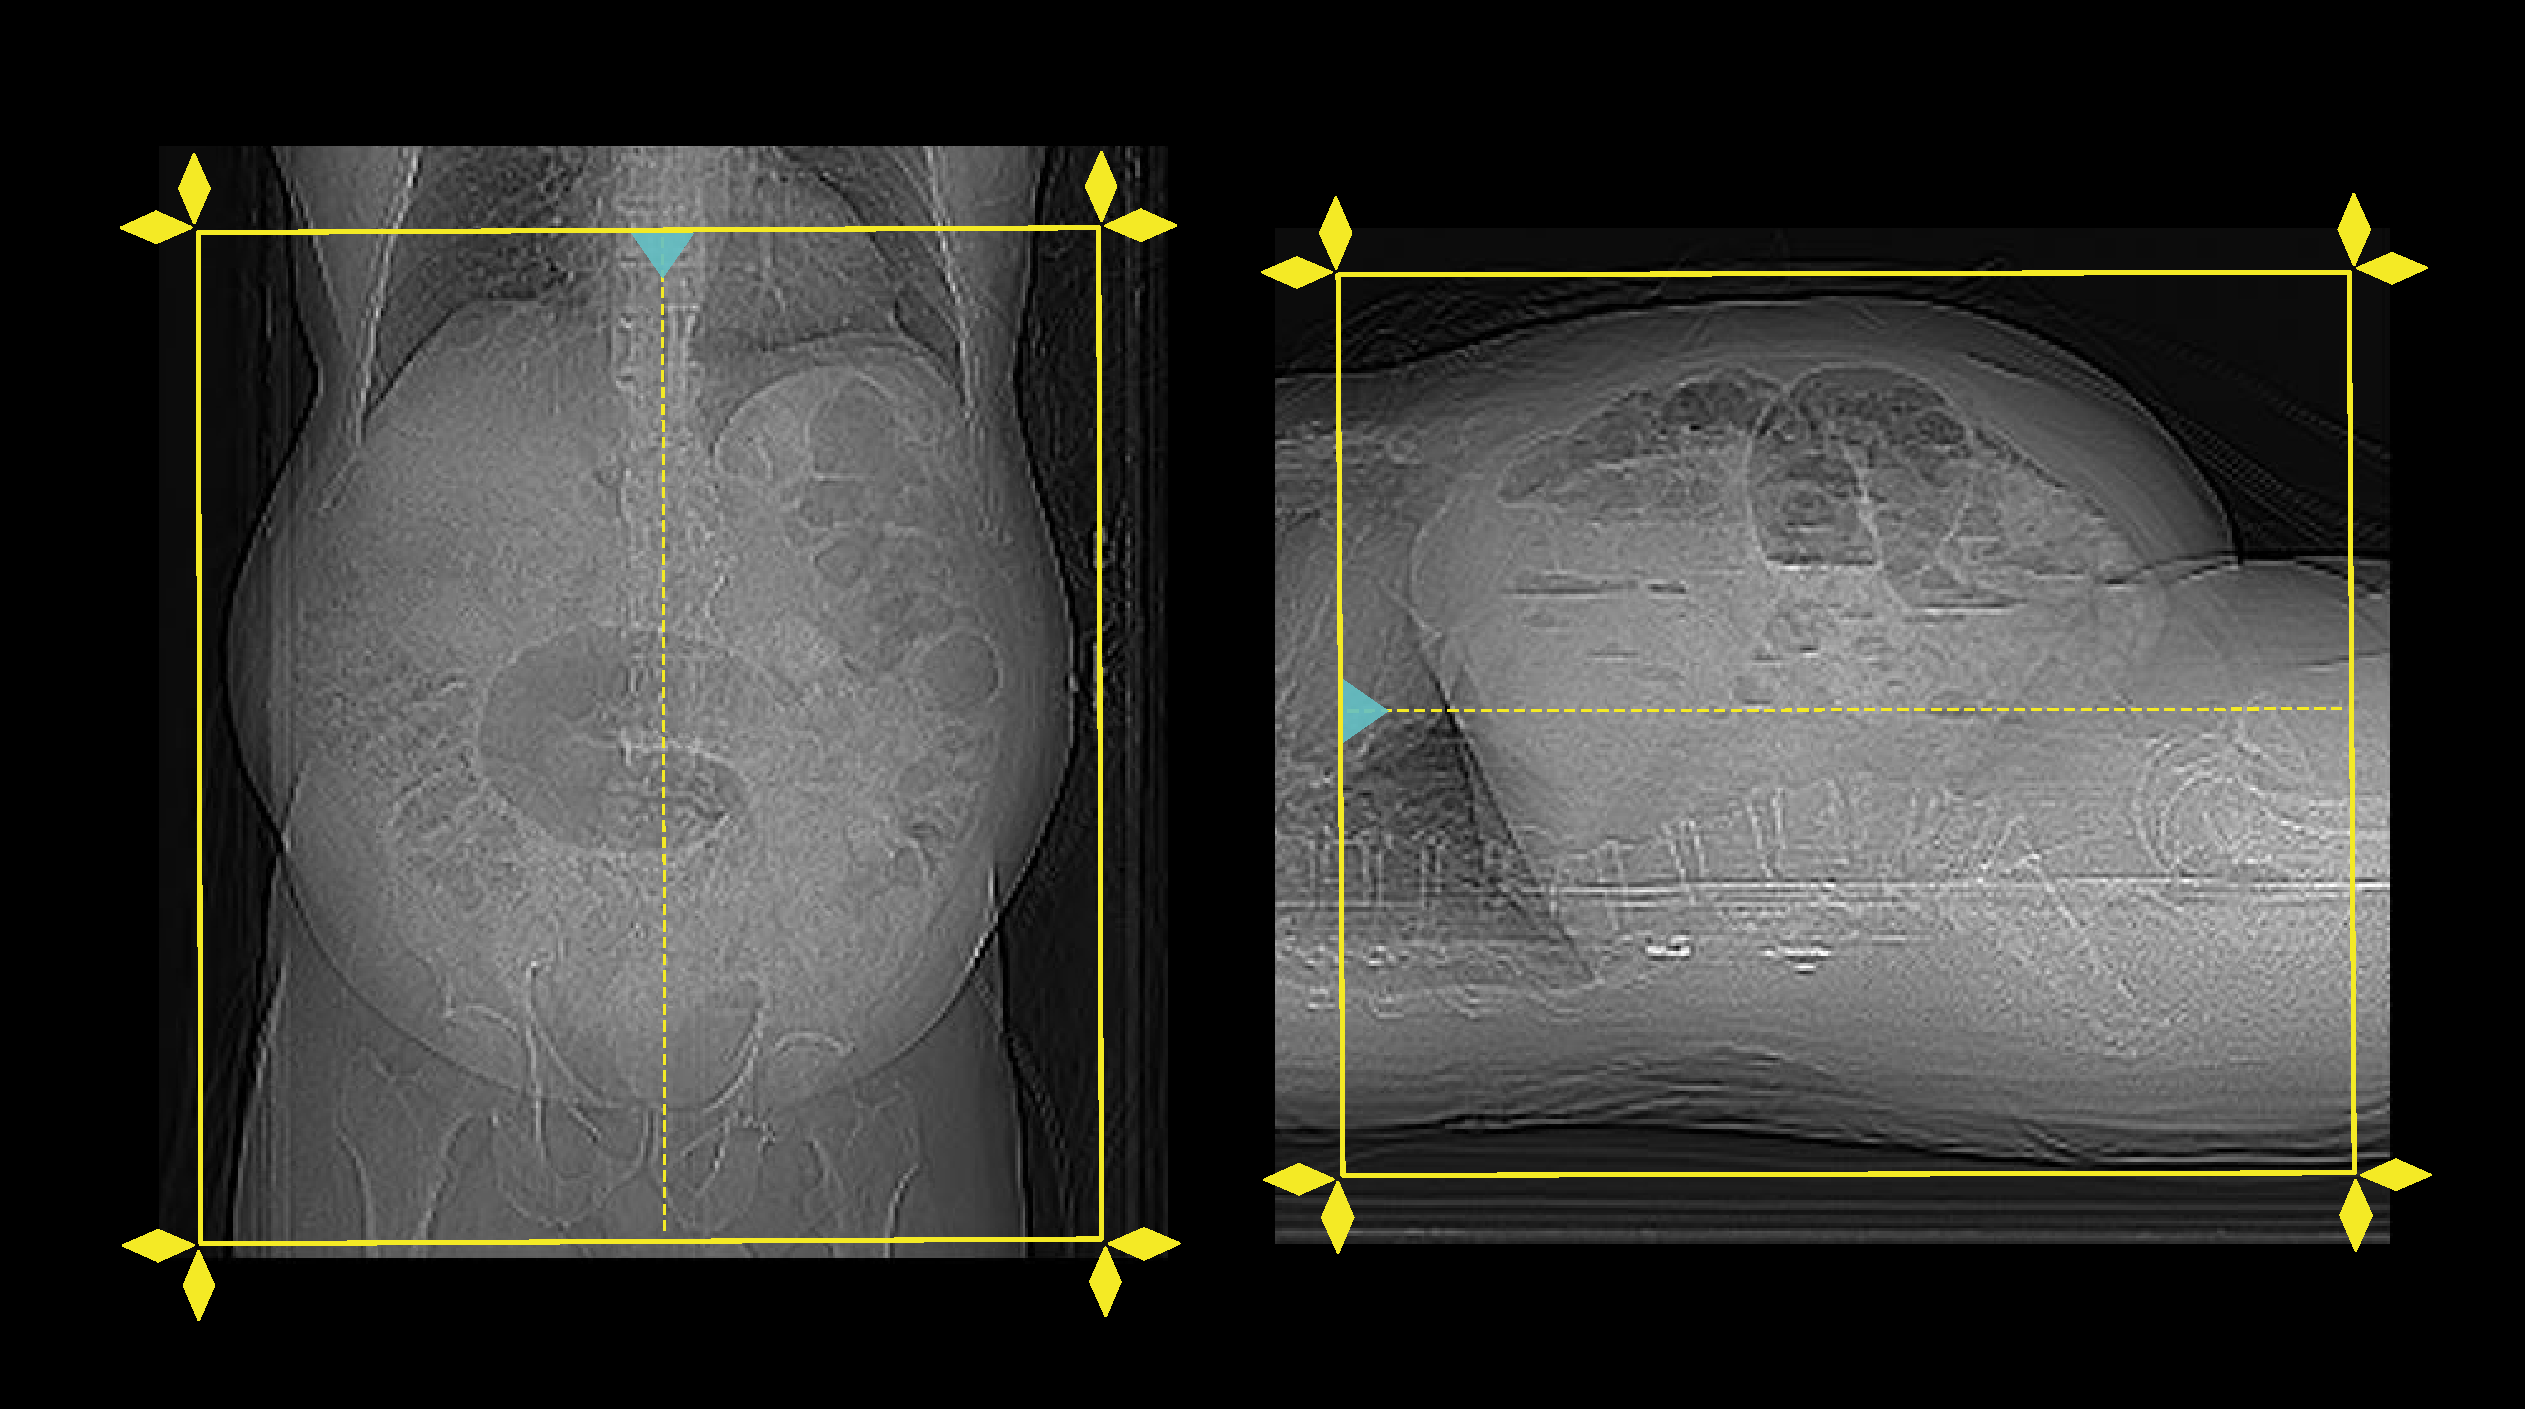

- Position the patient in feet first and supine.

- Center the scanning area in the scanner iso-center [6].

- Place both hands above the head.

- If abdomen or upper abdomen, plan the scan slab from the dome of the diagram to the upper margin of the sacroiliac joints. However, lower end point of the scan can be extended to the pelvic region according to diagnostic needs.

- If abdomen and pelvis, plan the scan slab from the dome of the diagram to a level just below the ischial tuberosities.